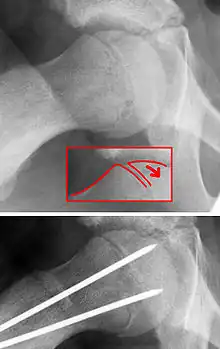

X-ray showing a slipped capital femoral epiphysis, before and after surgical fixation.

The disease can be treated with external in-situ pinning or open reduction and pinning. Consultation with an orthopaedic surgeon is necessary to repair this problem. Pinning the unaffected side prophylactically is not recommended for most patients, but may be appropriate if a second SCFE is very likely.[11]

Once SCFE is suspected, the patient should be non-weight bearing and remain on strict bed rest. In severe cases, after enough rest the patient may require physical therapy to regain strength and movement back to the leg. A SCFE is an orthopaedic emergency, as further slippage may result in occlusion of the blood supply and avascular necrosis (risk of 25 percent). Almost all cases require surgery, which usually involves the placement of one or two pins into the femoral head to prevent further slippage.[12] The recommended screw placement is in the center of the epiphysis and perpendicular to the physis.[13] Chances of a slippage occurring in the other hip are 20 percent within 18 months of diagnosis of the first slippage and consequently the opposite unaffected femur may also require pinning.

The risk of reducing this fracture includes the disruption of the blood supply to the bone. It has been shown in the past that attempts to correct the slippage by moving the head back into its correct position can cause the bone to die. Therefore the head of the femur is usually pinned 'as is'. A small incision is made in the outer side of the upper thigh and metal pins are placed through the femoral neck and into the head of the femur. A dressing covers the wound.